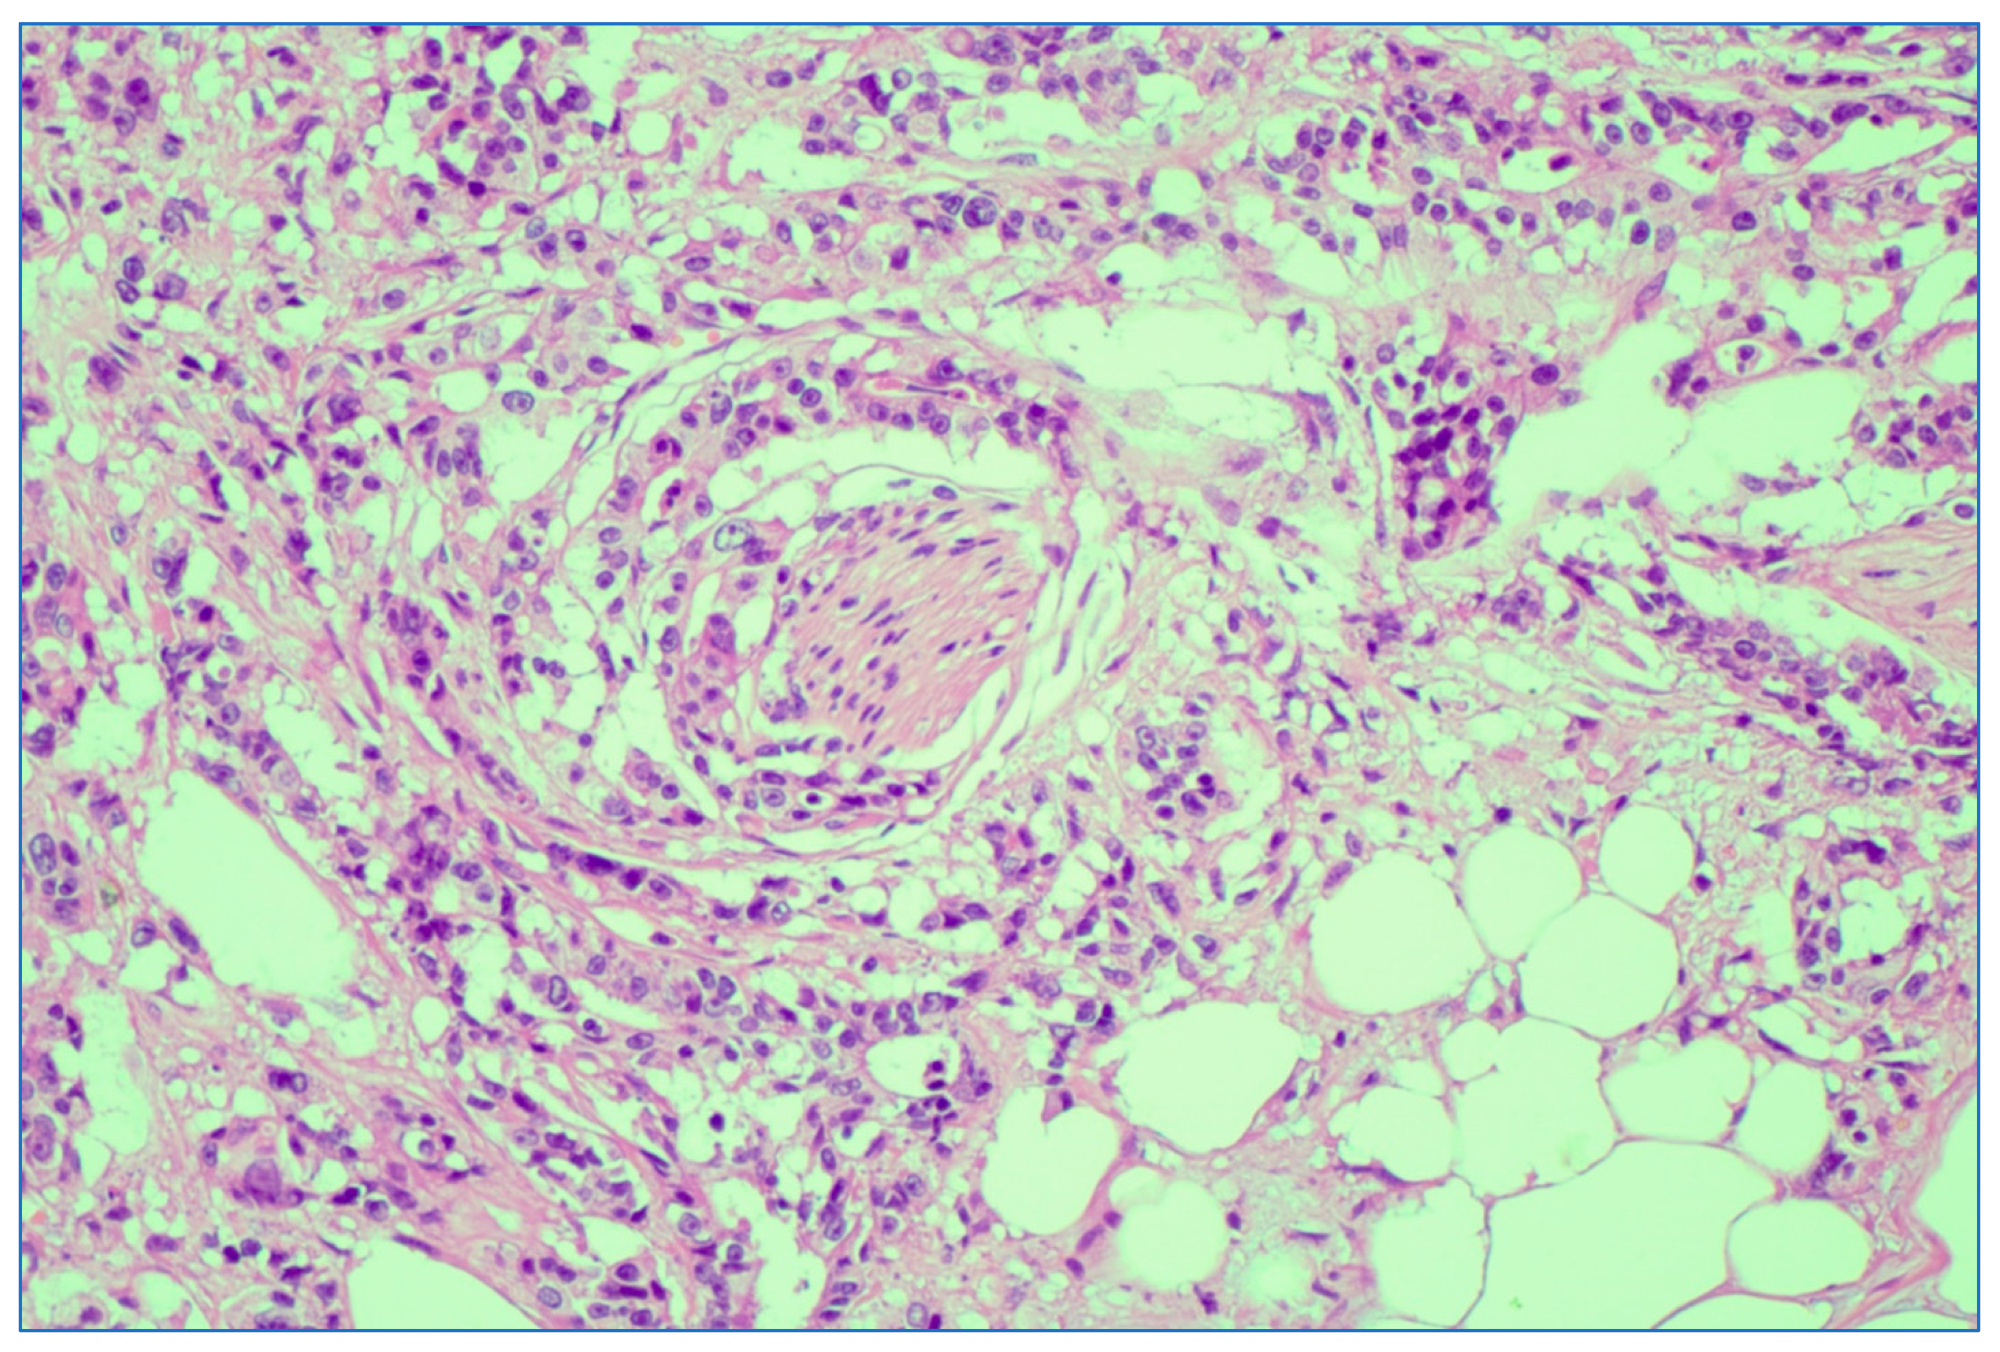

Figure 8.

Depiction of perineural invasion; rectal adenocarcinoma. HE stain × 5 magnification.